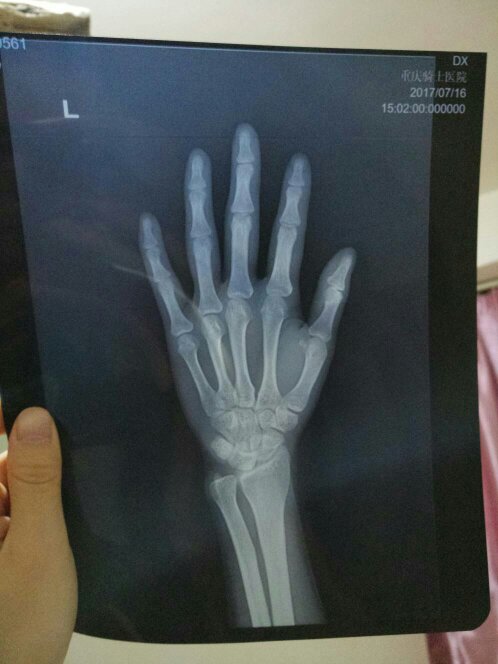

想要检查骨骺线是否已经闭合,通过拍X线片就可以得到确认,为了明确骨骺线是否完全闭合要拍正侧位,也就是拍两张片子拍两张片子的价钱从低往高,不同级别的医院收费不一样,从县级医院一般都是二级医院,两张片子收费大约是在100150元之间市级医院大部分都是三级医院,两张片子是在150200元之间。

骨骺拍片一般需要300元左右以下是一些关于骨骺拍片费用的具体说明拍片类型骨骺线是否闭合通常通过拍摄四肢X光片来检查费用范围在正规医院放射科进行此项检查,费用大约是300元建议为确保检查的准确性和安全性,建议去正规医院放射科进行拍片请注意,具体费用可能会因地区医院级别和设备等因素有所不同,建议在拍片前咨询医院工作人员以获取准确费用信息。

检查骨骺线是否闭合的费用大约在100元左右这一费用主要是基于进行X光片的检查,该检查用于观察骨骼的生长情况和骨骺线的闭合状态具体费用可能会因地区医院等级或检查设备的不同而略有差异,但通常不会相差太大在进行此类检查时,建议咨询当地医院或医疗机构以获取最准确的费用信息。

1 骨骺线检查是通过X光对特定骨骼部位进行成像,以评估骨骼生长和闭合情况的一种方法2 检查费用受地区医疗成本医院等级和使用的X光设备等因素影响,因此可能会有所不同3 一般来说,拍摄一个部位的骨骺线费用大约是50元人民币,如果需要检查多个部位,费用会相应增加4 对于16岁以下的儿童。